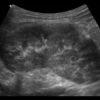

– Thận xoa trục, 2 cực dưới thận liên tục với nhau vắt ngang qua phía trước cột sống bởi nhu mô thận hay tổ chức xơ.

– Trên lát cắt dọc: không thấy rõ ranh giới cực dưới 2 thận.

– Trên lát cắt ngang qua đường giữa: 2 thận dính nhau, vắt ngang qua cột sống, phía trước động mạch chủ bụng.

– Có thể kèm theo các bất thường bất thường đường bài xuất, thận đôi, sỏi, nang thận hoặc u thận, sỏi gây giãn đường bài xuất.

=> Case lâm sàng 2: